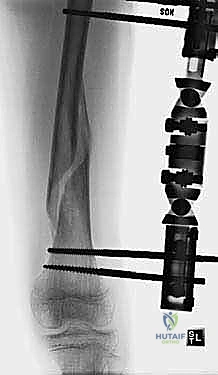

التثبيت الخارجي هو تقنية جراحية يتم فيها إدخال دبابيس أو براغي معدنية خاصة من خلال الجلد إلى العظم السليم أعلى وأسفل منطقة الكسر. يتم بعد ذلك توصيل هذه الدبابيس بإطار معدني أو كربوني صلب خارج الجسم.

3. إدخال الدبابيس المعدنية (Pin Insertion)

يتم عمل شقوق دقيقة جداً في الجلد (مليمترات معدودة). وباستخدام مثقاب جراحي خاص، يتم إدخال البراغي في العظم السليم أعلى الكسر وأسفله. يحرص الدكتور هطيف بدقة متناهية على تجنب الأعصاب، الأوعية الدموية، ومراكز النمو.

4. تركيب الإطار الخارجي (Frame Assembly)

يتم توصيل البراغي البارزة من الجلد بقضبان خارجية (غالباً مصنوعة من ألياف الكربون الخفيفة والقوية، أو التيتانيوم). يتم شد هذه القضبان وتثبيتها بقوة لضمان استقرار الكسر تماماً.